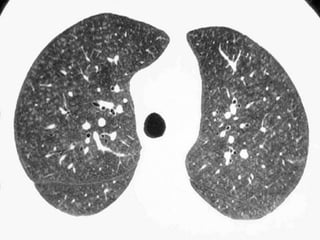

Pathology in whiteAreas Alveolitis / Pneumonitis Ground glass desquamative intertitial pneumoinia (DIP) nonspecific interstitial pneumonia (NSIP) organizing pneumonia In expiration both areas (white and black) decrease in volume and increase in density DECREASE IN CONTRAST DIFFERENCES